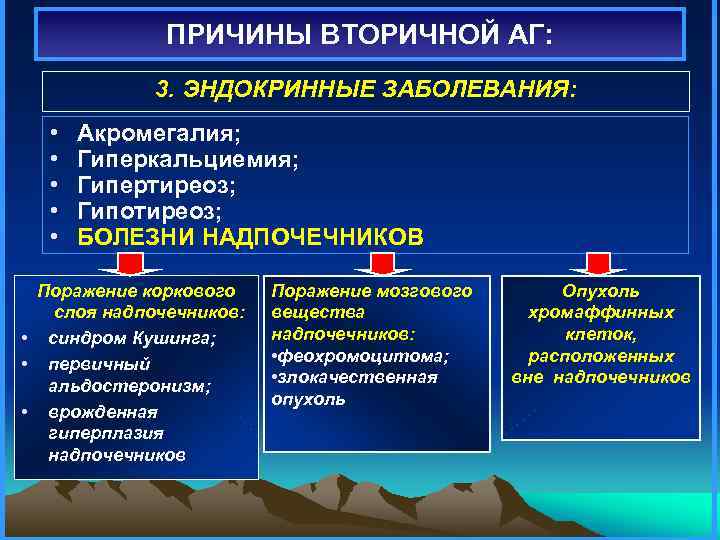

ПРИЧИНЫ ВТОРИЧНОЙ АГ: 3. ЭНДОКРИННЫЕ ЗАБОЛЕВАНИЯ: • • • Акромегалия; Гиперкальциемия; Гипертиреоз; Гипотиреоз; БОЛЕЗНИ НАДПОЧЕЧНИКОВ Поражение коркового слоя надпочечников: • синдром Кушинга; • первичный альдостеронизм; • врожденная гиперплазия надпочечников Поражение мозгового вещества надпочечников: • феохромоцитома; • злокачественная опухоль Опухоль хромаффинных клеток, расположенных вне надпочечников

ПРИЧИНЫ ВТОРИЧНОЙ АГ: 3. ЭНДОКРИННЫЕ ЗАБОЛЕВАНИЯ: • • • Акромегалия; Гиперкальциемия; Гипертиреоз; Гипотиреоз; БОЛЕЗНИ НАДПОЧЕЧНИКОВ Поражение коркового слоя надпочечников: • синдром Кушинга; • первичный альдостеронизм; • врожденная гиперплазия надпочечников Поражение мозгового вещества надпочечников: • феохромоцитома; • злокачественная опухоль Опухоль хромаффинных клеток, расположенных вне надпочечников